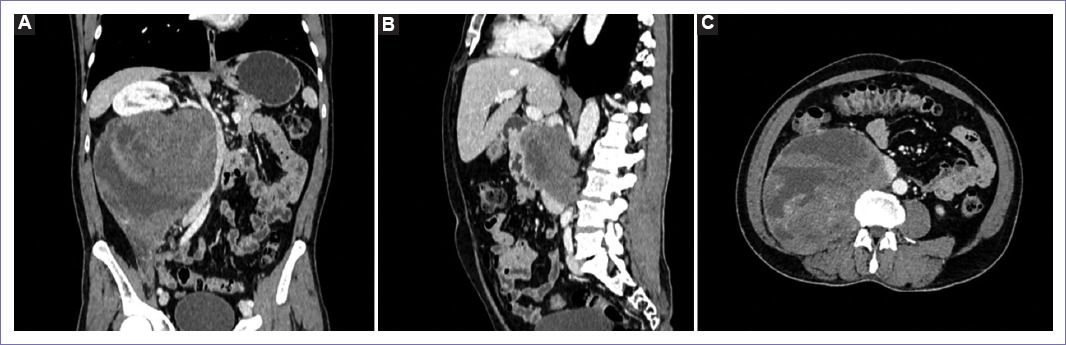

Figura 1 Tomografía espiral multicorte de abdomen y pelvis al ingreso. A: en vista coronal se observa una tumoración de aspecto neoproliferativo a nivel retroperitoneal derecho, de densidad heterogénea con áreas hipodensas (sugiere necrosis), mide 17 x 17 x 12 cm y presenta captación heterogénea del contraste. B: en vista sagital se observa el desplazamiento craneal del riñón derecho, por la masa retroperitoneal anterior a la vena cava inferior. C: en vista sagital se observa el efecto lítico a nivel de cuerpo vertebral de L2 y mala interfase con músculo psoas.

Figura 4 Tomografía espiral multicorte de abdomen y pelvis a los cinco meses. A: masa sólida en el lado derecho del retroperitoneo, muestra captación heterogénea de la sustancia de contraste, mide 21 x 22 x 15 cm, ejerce efecto de masa desplazando hacia cefálico el hilio y riñón derecho, sin evidencia de infiltrarlo, así mismo desplaza el uréter hacia ventral en todo su trayecto; desplaza hacia contralateral la aorta abdominal, páncreas y asas delgadas, contacta la unión de la venas ilíacas. B: el trayecto de la vena cava inferior no se logra representar adecuadamente, por la infiltración de la masa retroperitoneal. C: masa que infiltra el músculo psoas, así como el cuerpo vertebral L2, condicionando lesiones líticas, además se extiende hacia el neuroforamen L2-L3 derecho.